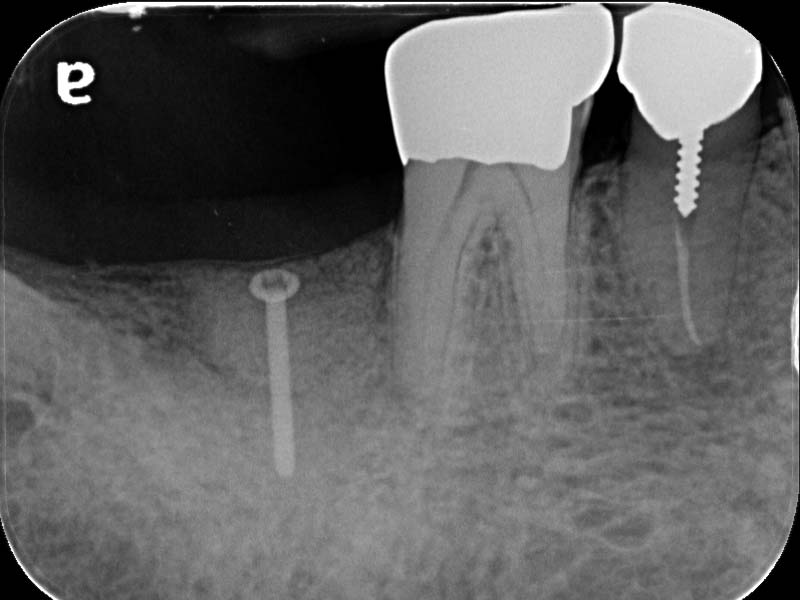

圖例為案例分享:

術前

帳棚釘+骨粉+再生膜術後6個月

植牙術後5.5個月

帳棚釘+骨粉+再生膜術後7個月

植牙當日